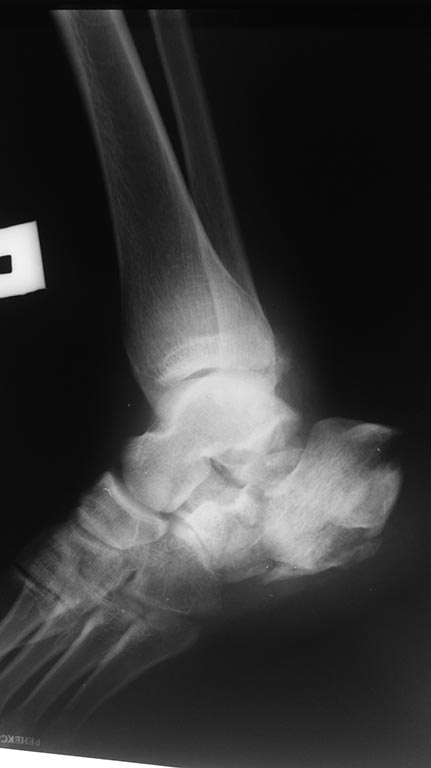

Имя     : 20170317_184700.jpg

Тип     : image/jpeg

Url     : http://weborto.net:8080/pipermail/ortho/attachments/20170320/7e16afb9/attachment-0004.jpg